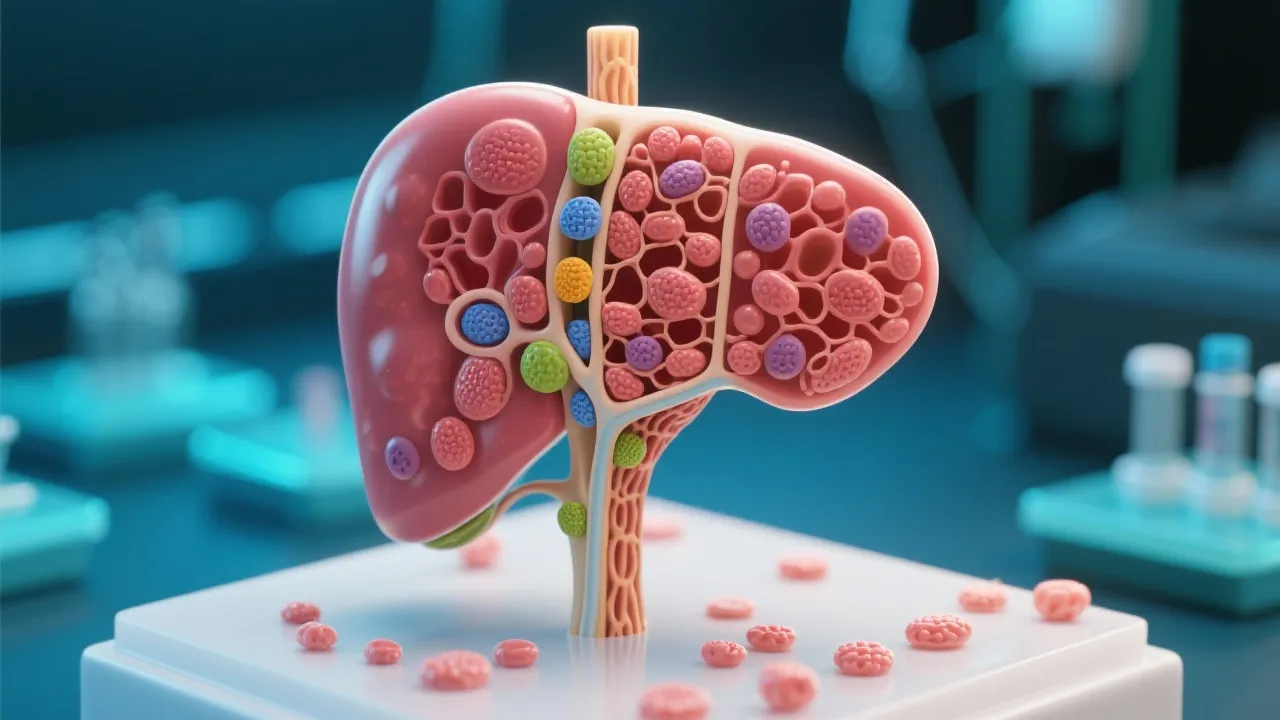

This article provides an expert overview of the importance of Non Alcoholic Fatty Liver Disease (NAFLD) models in drug discovery. Understanding NAFLD is crucial in addressing a significant public health issue affecting millions globally. Focusing on the development and utilization of various NAFLD models, the text examines current strategies and methodologies, aiming to offer insights into future drug development for this prevalent liver condition.

Non Alcoholic Fatty Liver Disease (NAFLD) represents a spectrum of liver conditions characterized by excessive fat accumulation in the liver cells of individuals who consume little to no alcohol. Initially considered a benign condition, NAFLD is now increasingly recognized as a major public health concern, affecting approximately 25% of the global population. The disease can progress from simple hepatic steatosis to more severe forms, including non-alcoholic steatohepatitis (NASH), which can further lead to liver fibrosis, cirrhosis, and even hepatocellular carcinoma, a primary form of liver cancer. The growing prevalence of NAFLD is closely linked to the obesity epidemic, rising incidence of type 2 diabetes, and a sedentary lifestyle, which pose an ever-growing challenge for healthcare systems worldwide.

The development of reliable and effective NAFLD models is pivotal for advancing drug discovery efforts. These models provide researchers with valuable insights into the pathogenesis of the disease, enabling them to test potential therapeutic agents in a controlled environment. They help bridge the gap between understanding the biological mechanisms of NAFLD and translating that knowledge into effective treatments. Through various models, from in vitro systems to advanced animal subjects, researchers can simulate the disease's progression and response to treatment, which is crucial for developing targeted therapies. The urgency for effective NAFLD treatments has led to an increased focus on discovering novel pharmacological interventions, particularly as the complications associated with advanced liver disease can severely impact patients' quality of life and lead to significant healthcare costs.

NAFLD models are diverse and can be classified into several types, including: